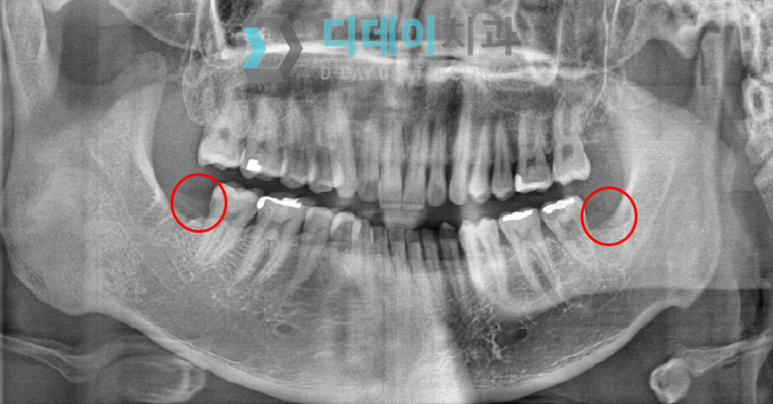

아래는 2개의 사랑니를 모두 발치한 후입니다.

강남사랑니발치

전과 후 사진을 비교하면 그 차이가 또렷이 보이시지요?

2번째 사랑니 발치를 한 후, '이제껏 받은 치과 치료 중에서 안 아픈 적은 처음이에요.', '충치도 사라졌으니 편안하게 밥 먹을 수 있겠네요.'라고 말씀해 주셨답니다.